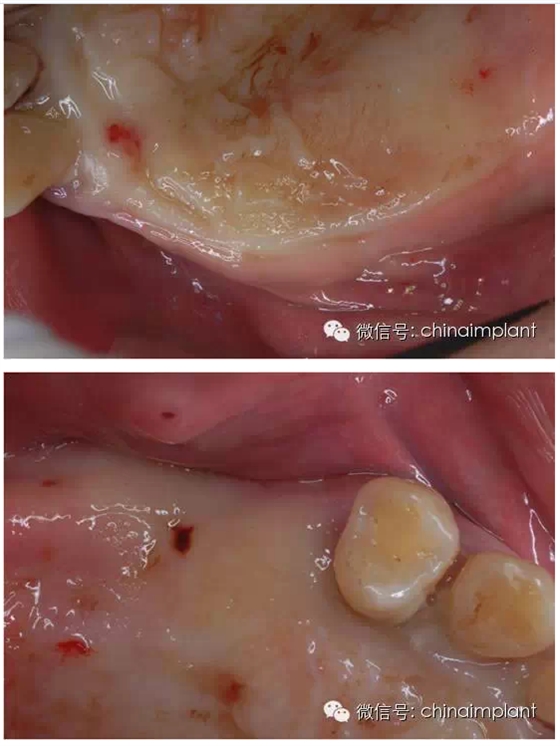

之前針對全口無牙進(jìn)行種植修復(fù)的案例中,因?yàn)轭M骨的原因,后期使用橋冠修復(fù)時(shí),一般是3部分(兩側(cè),磨牙,前牙),最近的案例中修復(fù)是一般都是做一體式的橋冠,現(xiàn)在從臨床的修復(fù)案例來看,沒有什么問題。

之前的時(shí)候,使用圓錐形基臺,但是附著的力量容易分散。(最近由于費(fèi)用的問題多使用UCLA形態(tài)的基臺)